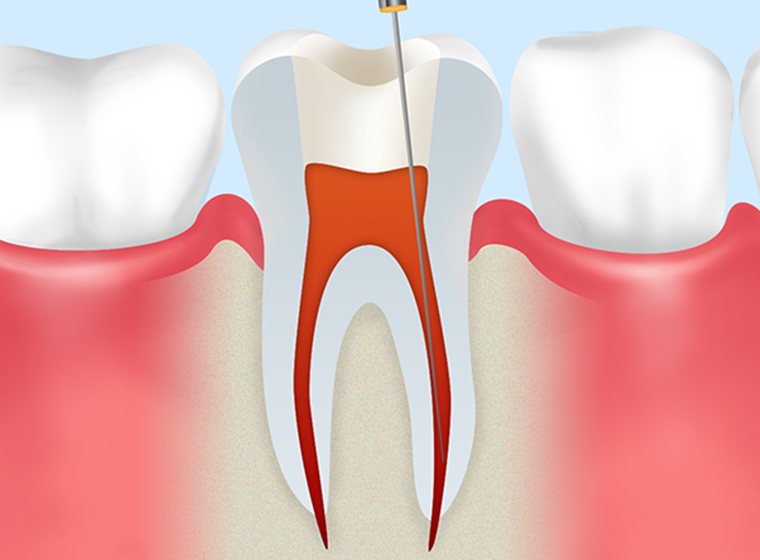

- STEP2

根管内の洗浄と計測 -